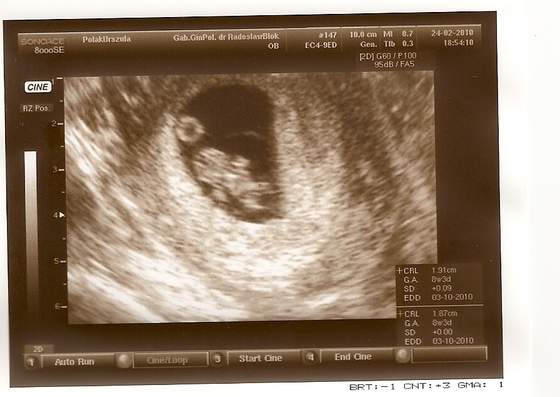

Jak to mój mąż wuefista stwierdził: widać już łapki i piłkę do ręcznej... :-)

Już ma prawie 2 cm... :tak:

• skanuj0002.jpg

skanuj0002.jpg

28,1 KB · Wyświetleń: 155

• skanuj0004.jpg

skanuj0004.jpg

27,5 KB · Wyświetleń: 144